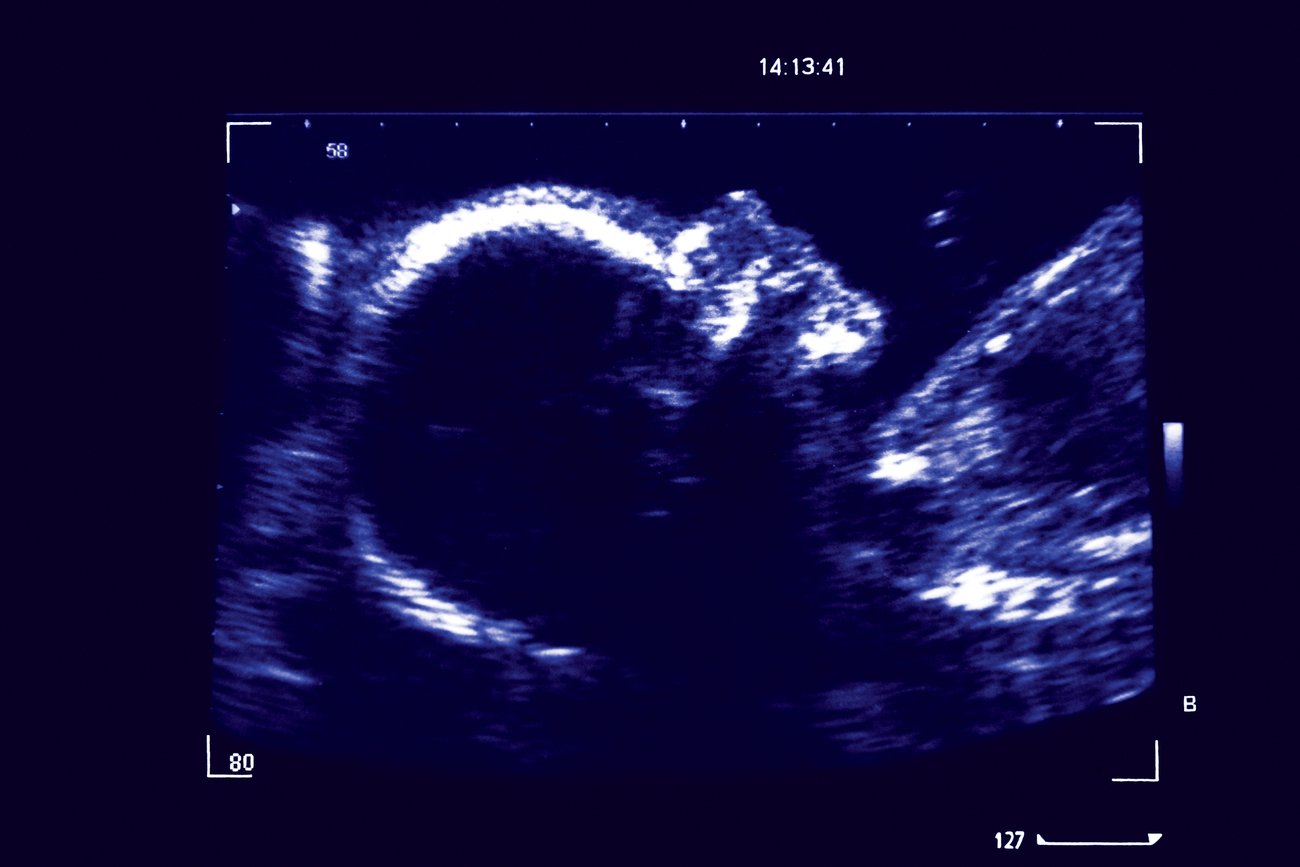

Jetzt wird's spannend! Ungefähr ab der 5. Schwangerschaftswoche (SSW), gerechnet ab dem ersten Tag deiner letzten Periode, kann man mit einem vaginalen Ultraschall (also einem Ultraschall, der von innen gemacht wird) eine Fruchthöhle erkennen. Stell dir das vor wie eine kleine Blase, die das zukünftige Baby-Zuhause markiert. Manchmal – und das ist schon ein kleiner Jackpot – kann man sogar schon den Dottersack sehen. Das ist quasi die erste Mini-Mahlzeit für deinen kleinen Mitbewohner.

Das Herzchen schlägt: Woche 6 und 7

Trommelwirbel! Ab der 6. oder 7. SSW kommt der Moment, auf den alle warten: Das kleine Herzchen beginnt zu schlagen! Das ist wie ein Mini-Konzert in deinem Bauch. Bei einem Ultraschall kann man diesen Herzschlag dann in der Regel deutlich sehen und hören. Viele Frauen beschreiben diesen Moment als unglaublich emotional und beruhigend. Stell dir vor, du bist im Kino und siehst den ersten Trailer deines absoluten Lieblingsfilms – Gänsehaut garantiert!